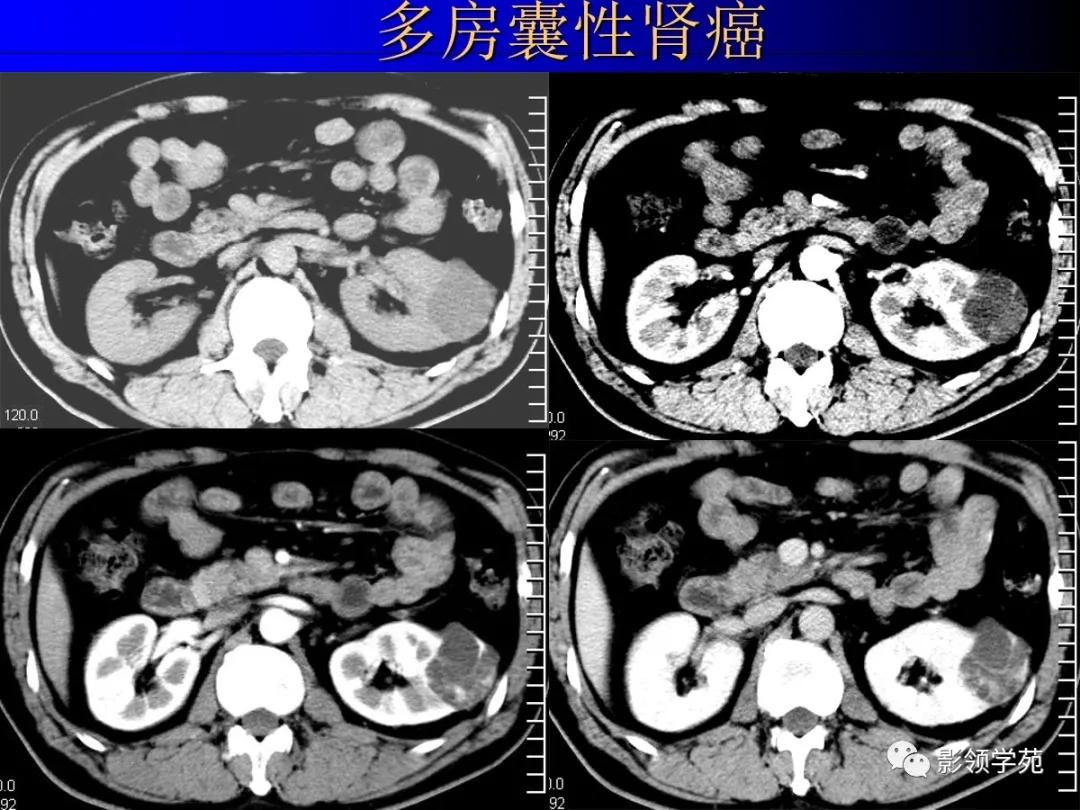

4、多房囊性肾瘤multilocular cystic nephroma

非遗传性的囊性病变。

囊壁内衬立方或扁平上皮。

多房囊腔间互不交通,伴完整的纤维分隔。

恶性者即多房囊性肾癌。

12、肾癌囊变和多房囊性肾癌

多房囊性肾癌有完整分隔

1、囊性肾癌的临床及病理

好发于中老年人,约占肾癌的2%~15%。病理组织学可将囊性肾癌分为4种类型:

②多房囊肿性囊性肾癌

2、囊性肾癌与肾癌囊变是两个不同的概念

前者是以囊性方式生长为主的肿瘤,后者是实体癌的广泛出血、坏死囊变而成。据Hartman等(1986)统计,囊性肾癌占肾癌总数的10%~15%。囊性肾癌的发病机制总体上还不很清楚,但认为可能是

3、囊性肾癌的CT表现

囊性肾癌的CT表现各异,根据本组影像结果显示,囊性肾癌主要有以下CT表现: